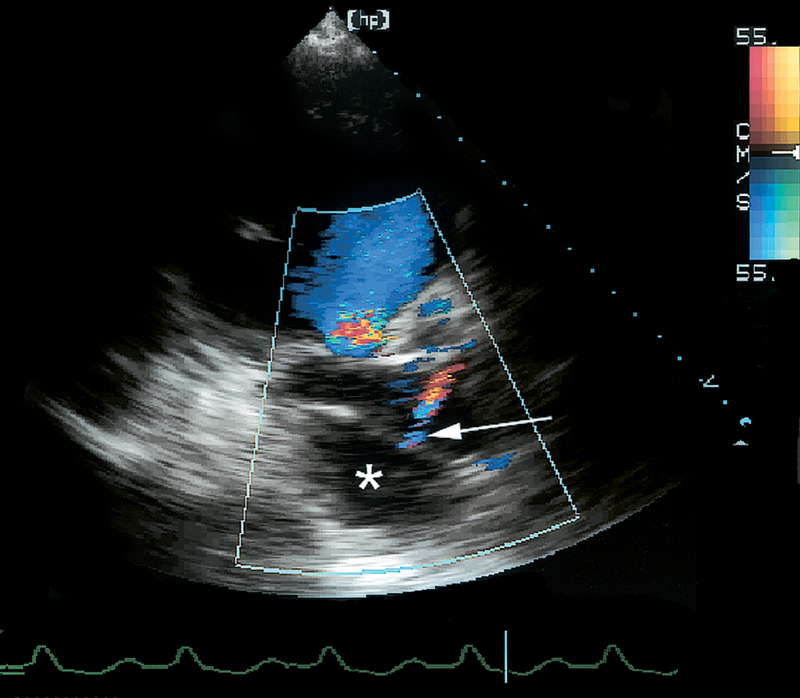

فحوصات تشخيصية لبعض امراض القلب والشرايين التاجية